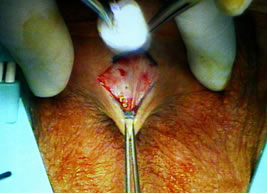

Выполнен поперечный доступ в пеноскротальном углу. Острым путем выделена и мобилизована уретра. Уретра взята на мягкую держалку в бульбозном отделе. С помощью гибкой ленты измерена окружность уретры (предварительно установлен катетер №18 F).

Основные этапы операции.